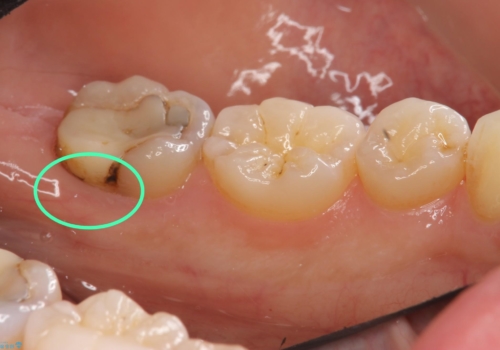

他院でつめていたものは、セメントで、一時的な詰め物がなされていました。(中は虫歯になっていました。)

虫歯を取ると、歯ぐきの奥深くまで虫歯になっており、そのままではきちんと修復することが難しい状態でした。

①虫歯を無視してとりあえずつめる(必ず虫歯になり、進行するため神経を取らなければいけなくなる)

:マージン(キワ)はぴったりは合わないため、長期的な予後は見込めない。=歯は長く持たない。